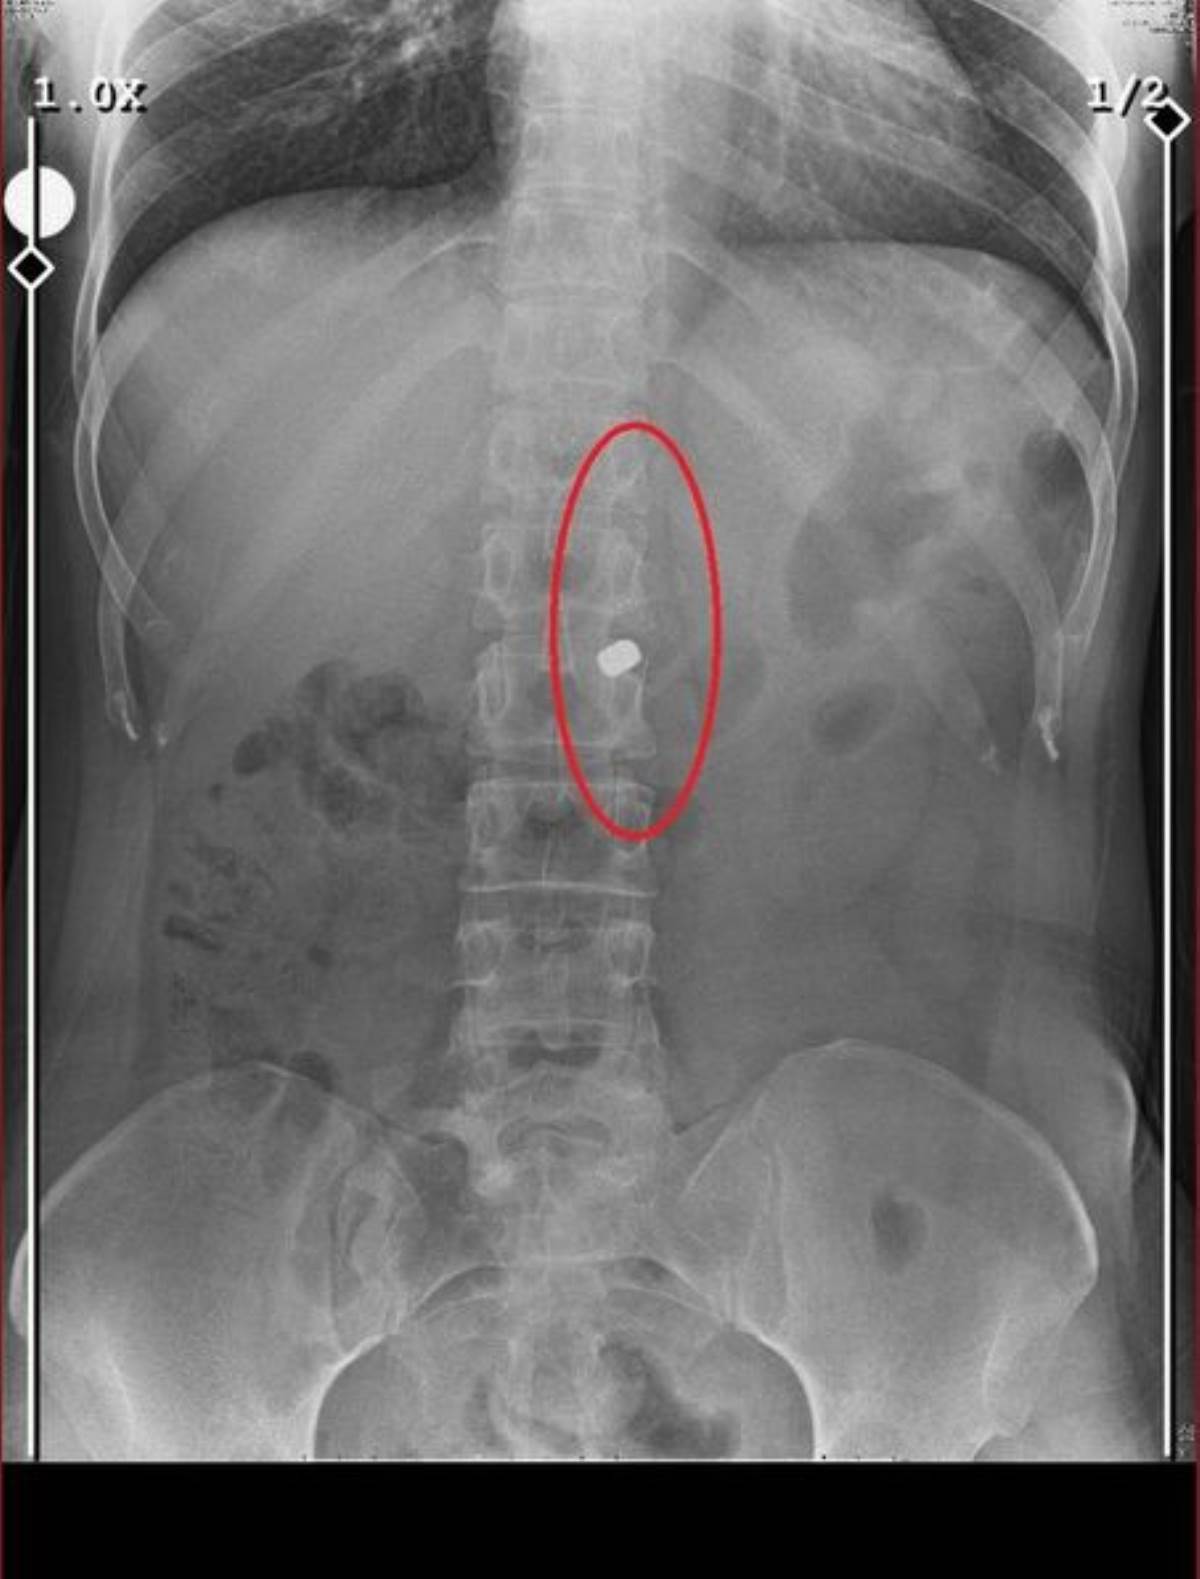

“Bildiğiniz cehennemi yaşadım. Nedenini bilmiyorum ama önce arkadaşını vurdu. 3 tane mermiyle öldü zaten arkadaşı. 2 tane daha ‘Garanti olsun’ dedi, üstüne sıktı. Onu daha hızlı vurdu, benimle bayağı kedinin fareyle oynadığı gibi oynadı. Bir saat sürdü beni vurması, 8 mermi sıktı. 1’i çıktı vücudumdan, 1’ini hastanede aldılar. 6 tane mermi hala vücudumda onunla yaşıyorum."

Vücudundaki 6 mermiyle yaşamaya devam ettiğimi söyleyen F.O., “6 tane mermiyle yaşıyorum vücudumda. Ben de inanamıyorum nasıl yaşadığıma. Nasıl bir mucize olduğuma. Bildiğin bir mucize bu yani. Allah'ın mucizesi. 21 gün boyunca bildiğiniz bir psikolojik savaş verdim orada onunla. Hem bedenen savaş verdim. Cinsel istismara uğruyordum. Hem psikolojik işkence gördüm. Kızım için yaşadım. Bir şekilde yaşadım” ifadelerini kullandı.